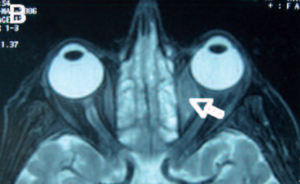

اللمفوما المحجرية، (Orbital lymphoma)،(Lymphoma orbitalis) هو نوع شائع من اللمفوما اللاهودجكينية التي تحدث بالقرب من العين أو عليها. تشمل الأعراض الشائعة انخفاض الرؤية والتهاب العنبية . يمكن تشخيص اللمفوما المحجرية عن طريق خزعة من العين وعادة ما يتم علاجه بالعلاج الإشعاعي أو بالاشتراك مع العلاج الكيميائي

تشمل العلامات الأولية الواضحة للمفوما المحجرية جحوظ العين وكتلة مرئية في العين. الأعراض ناتجة عن تأثير الكتلة .